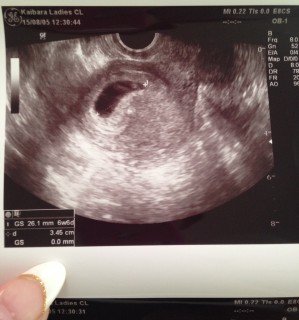

胎嚢の中の胎芽の真ん中が、チカチカして心拍確認が出来た時は本当に安堵しました。一度繋留流産経験していたので、夢にまでみた瞬間でした。胎嚢の大きさは23.4mmです。